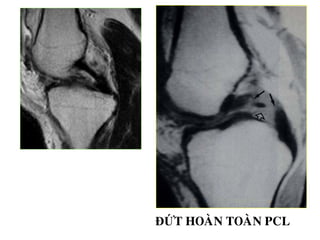

ĐỨT HOAØN TOAØN PCL